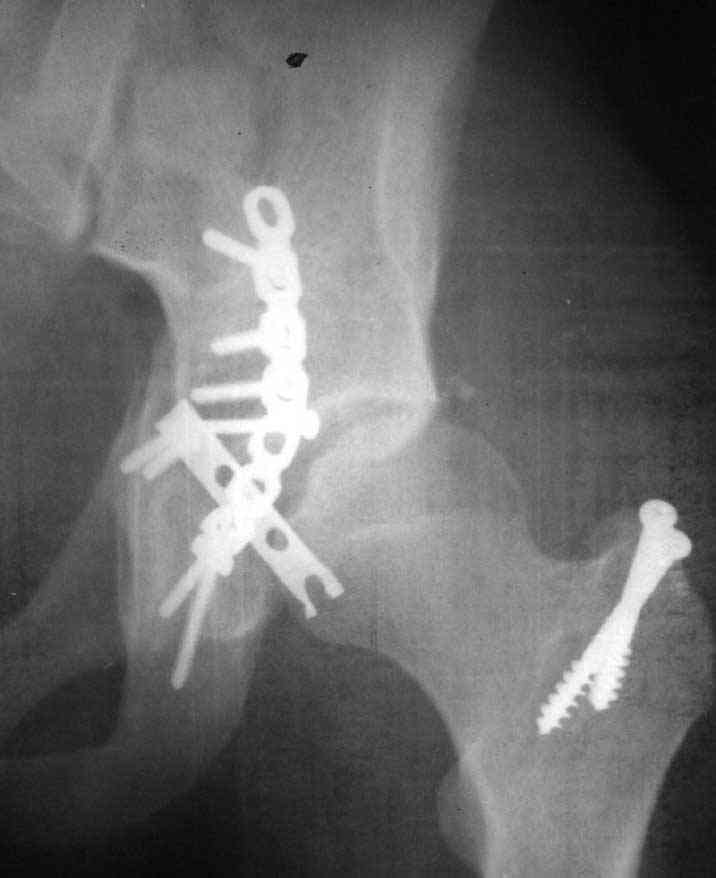

Open reduction and internal fixation was performed through posterior approach with trochanteric osteotomy. Extraction of the incarcerated fragment was very difficult, and then reduction of the femoral head also felt less easy than usual. After plate fixation, the head was found to subluxe on maximum internal rotation. However, it became more or less stable after fixation of the trochanteric osteotomy and reattachment of the rotators. Xray showed lateral displacement of the femoral head. CT was also performed and it confirmed the lateral displacement although I don't know if it could be termed subluxation. The flexion- extension ROM is 0-45 with some internal-external rotation, but the limitation is mostly by pain. I cannot explain this situation and would you like to hear your suggestions.

I am confident that I left no intraarticular fragments. Could the comminution in the anterior wall visible on CT be responsible for this?

I am planning to fix his concomitant tibia fracture within 3 days, and in the process perform an examination under anaesthesia. If the ROM is good, I may leave him alone. What do you think? I am sending the x ray and CT in 3 mails